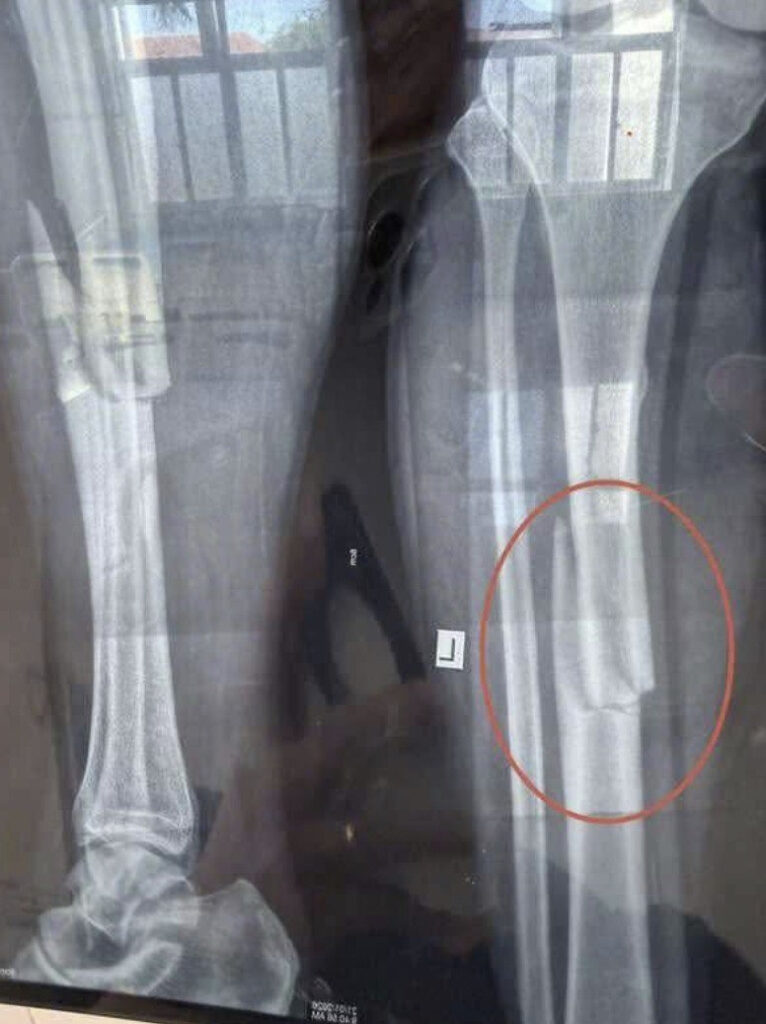

Vid – Hiên trường TNLĐ trong lúc làm việc